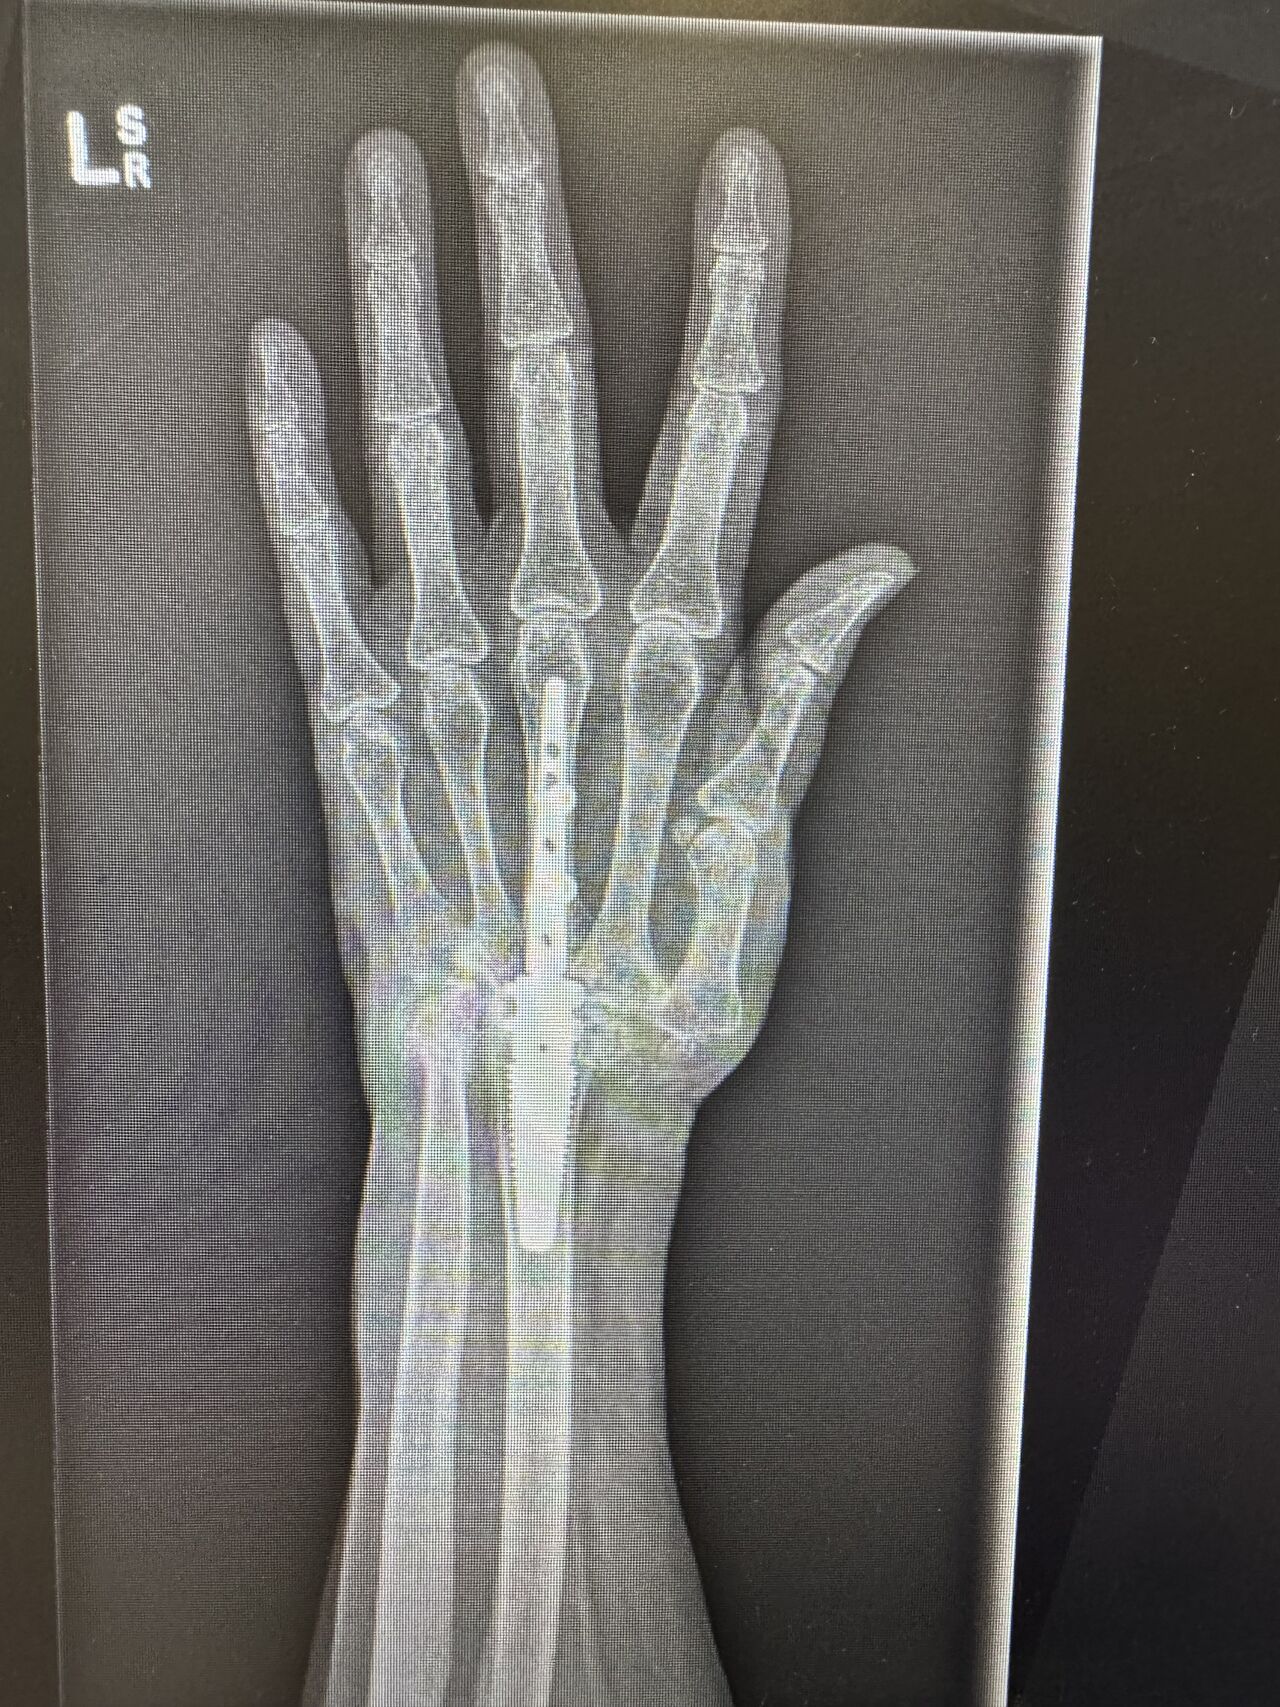

This challenging wrist reconstruction required a combination of advanced surgical techniques and careful multidisciplinary thinking:

• Deformity correction, drawing on Dr Sarah’s paediatric upper limb experience

• Use of the MotecWrist internal fusion system, keeping hardware within the wrist to minimise skin and tendon irritation

The outcome was a functional, sensate, and cosmetically acceptable hand—and, most importantly, a very happy patient.